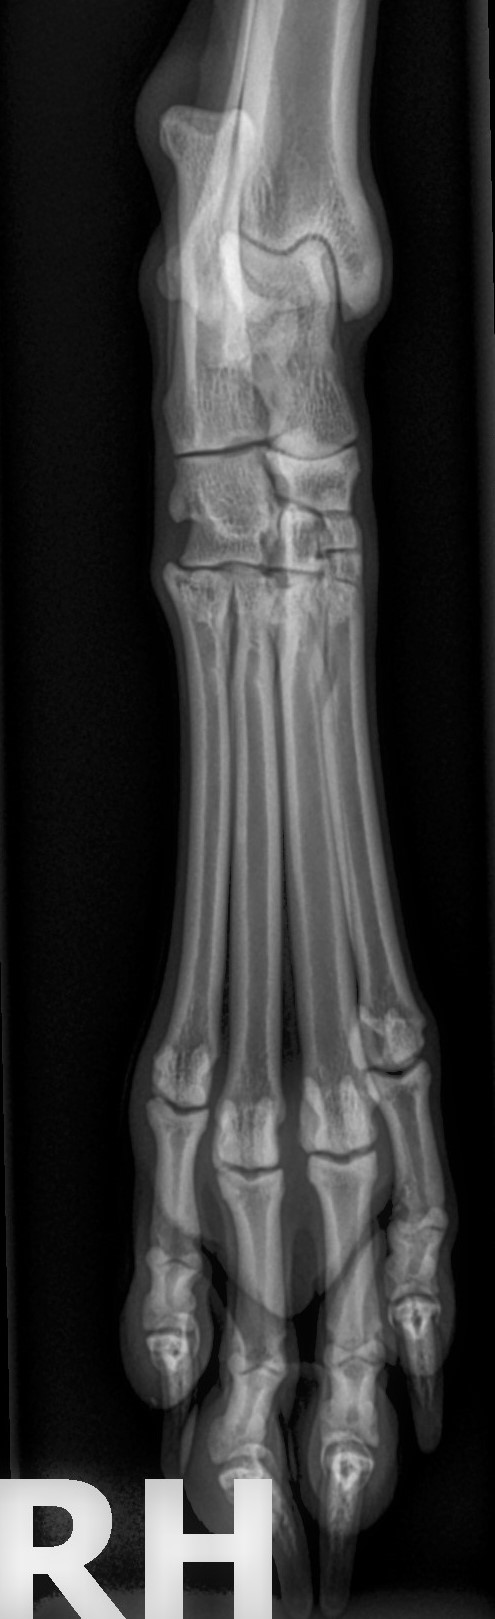

- Digitales Röntgen: Radiologische Untersuchungen stellen in der Orthopädie ein unabdingbares diagnostisches Verfahren dar und werden zur Detektion von knöchernen Veränderungen eingesetzt. Im Rahmen der Lahmheitsdiagnostik werden insbesondere die Gliedmaßen, die Hals-, Brust- und Lendenwirbelsäule sowie Teile des Schädels röntgenologisch auf mögliche pathologische Veränderungen untersucht.